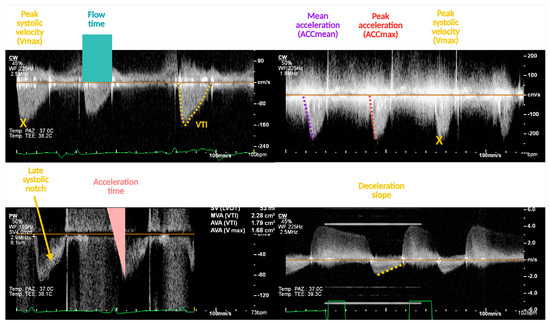

The Middle Meningeal Artery (MMA) occupies a pivotal role in the pathophysiology of migraine, functioning as a vascular and neuroimmune interface that precipitates the characteristic pulsatile pain. The inhibition of this pathophysiological cascade has been investigated as a therapeutic strategy. However, fewer than a dozen centers globally have disseminated procedural or mechanistic data. Given the nascency of this field and the imperative for standardization, the present review synthesizes mechanistic and clinical evidence underpinning intra-arterial pharmacological modulation of the MMA for migraine management. Methods: A focused narrative review was undertaken, drawing upon select but influential studies from pioneering research groups investigating intra-arterial interventions targeting the MMA. The extant literature was thematically categorized and organized according to the loci of cascade interruption and their corresponding clinical outcomes. Results: Since 2009, intra-arterial therapies for severe headache syndromes have evolved, initially utilizing nimodipine for vasospasm-related headaches, progressing to verapamil for reversible cerebral vasoconstriction, and more recently, lidocaine for refractory or status migrainosus, occasionally in conjunction with MMA embolization. Contemporary research uses language that conceptualizes migraine as an immunologically mediated neurovascular disorder, as opposed to a purely vascular or neuronal entity. Recent investigations have identified interleukins such as Interleukin-1β, Tumor Necrosis Factor-α, and Interleukin-6 as critical amplifiers of trigeminovascular activation. Purinergic signaling through the P2X3 receptor and the P2Y13 receptor, in conjunction with pituitary adenylate cyclase-activating polypeptide and vasoactive intestinal peptide pathways, has been implicated in the modulation of MMA excitability and neuropeptide release. The development of novel calcitonin gene-related peptide receptor antagonists, such as zavegepant, further substantiates the artery’s significance as a pharmacological target. Conclusions: These findings support a shift toward immune-modulating intra-arterial therapeutic strategies, with migraine interventions targeting cytokine and neuroimmune signaling within the MMA, rather than relying exclusively on vasodilatory mechanisms.